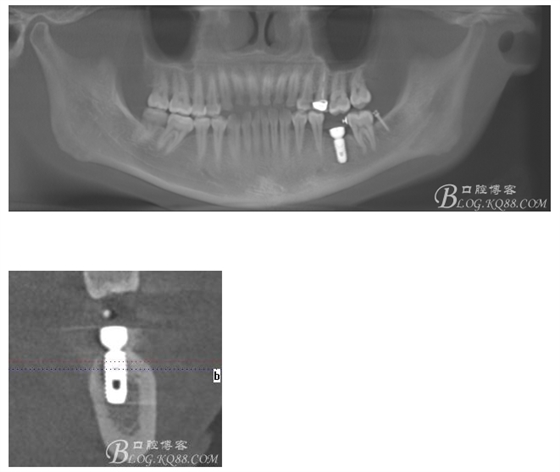

植入5.0X10mm植體

術后CT片

注:此時并不能拆除37遠中支抗釘,需等待取模型時再拆除支抗釘和舌側扣,防止37傾斜復發(fā)。